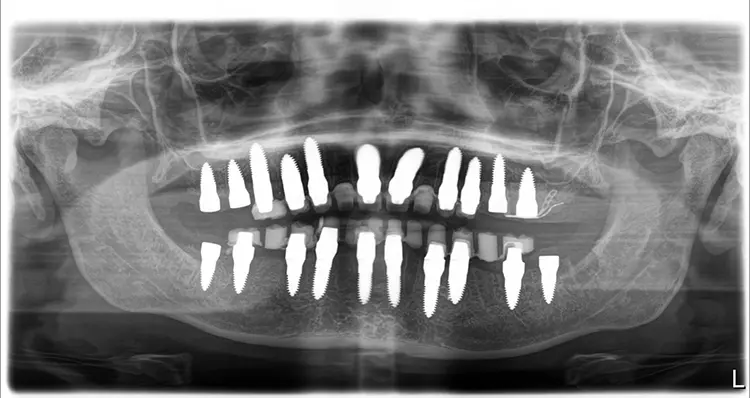

Abb. 18: OPG unmittelbar postoperativ nach Komplettsanierung innerhalb einer

Sitzung in ITN bei stark reduziertem Restgebiss. SDS

Abb. 18: OPG unmittelbar postoperativ nach Komplettsanierung innerhalb einer Sitzung in ITN bei stark reduziertem Restgebiss.